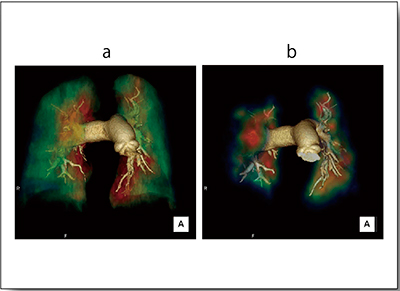

症例2はCTEPHである。CTAにLung PBVと肺血流シンチグラムをフュージョンした画像を比較したところ,灌流域のカラーマッピングはおおむね一致した(図3)。

図3 症例2:CTEPH(40歳代,女性)における

CTAとのフュージョン画像

a:CTA+Lung PBV

b:CTA+肺血流シンチグラム